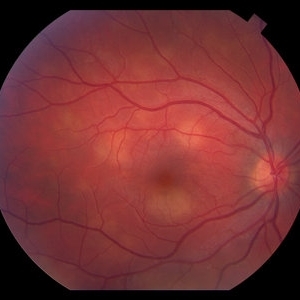

AMPPE

Apr 29 2014 by David W. Faber, MD

24-year-old female presented with central blurry vision for 3-5 days. Vision : OD 20/20, OS 20/100

Photographer: Jodi Schiele, Rocky Mountain Retina Consultants, Salt Lake City, Utah

Condition/keywords: acute multifocal placoid pigment epitheliopathy (AMPPE)